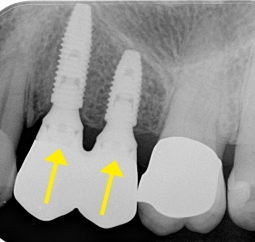

埋入位置(インプラントポジション)の大切さ

適当に骨がある位置にインプラントを埋入してしまうと、その上に接続される歯冠部の形態がおかしくなり、歯肉の炎症やかみ合せの不良が発生します。この状態からリカバリーするためには、インプラントを撤去したうえで失った骨や歯茎を再生させるなど、多くの時間と費用、肉体的苦痛が伴ってしまいます。

インプラントの埋入方向悪いため歯冠部の形態がおかしくインプラント周囲炎を起こしている